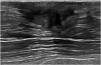

The nodular form is seen in patients with gynecomastia for less than 1 year.11 It is often referred as the early florid phase. Histologically, nodular gynecomastia is characterized by prominent ductal hyperplasia and cellular/proliferative stroma.4 It is worth noting that nodular gynecomastia is reversible if the underlying cause(s) is eliminated.4 Mammographically, it manifests as a nodular or fan-shaped subareolar opacity.4 On ultrasound, it appears as a disk-shaped, hypervascular, hypoechoic subareolar nodule surrounded by breast tissue 4,11 (Figs. 2 and 3).

60 year-old men with personal history of lung cancer presented with a left retroareolar lump and clear ipsilateral nipple discharge. On the low energy images (A, C), a nodular left subareolar opacity is seen. On the recombined images (B, D), it shows no enhancement. Sonographically (E), it corresponds to a hypoechoic subareolar nodule surrounded by breast tissue. Asymmetrical gynecomastia is also evident on CT images (F). Findings are suggestive of nodular pattern gynecomastia.

60 year-old male, HIV positive, presented with a right retroareolar mass and clear nipple discharge. No lymphadenopathies on physical exam. On the low energy right CC image (B), a nodular subareolar image can be seen. On the recombined images (A, C), a progressive mass enhancement is depicted. Note the increased in conspicuity at the last performed view (R-ML). On ultrasound (D), a hypoechoic subareolar nodule surrounded by breast tissue is shown. A 14G core needle biopsy confirmed the diagnosis of nodular gynecomastia.